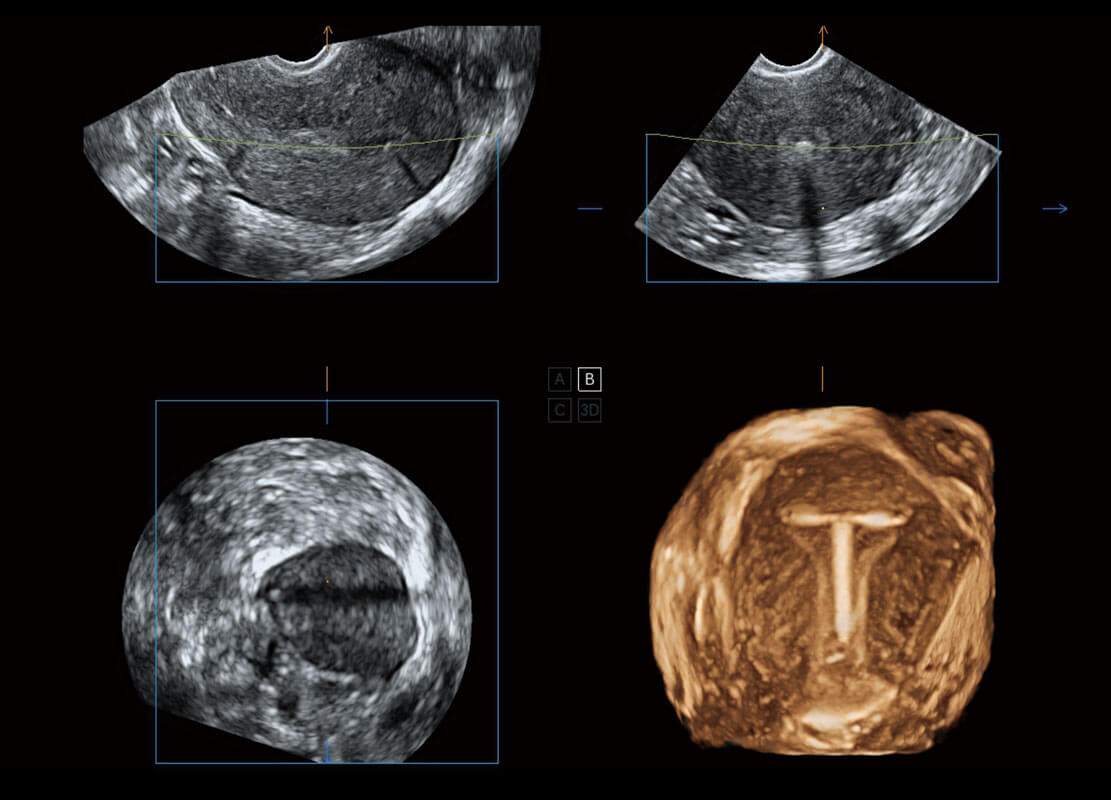

盆底超声

P60为盆底超声检查提供应用方案,多种腔内及腹部容积探头提供从二维、三维到四维的优异图像品质,实时快速三维容积数据获取,专业的测量工具包等人性化设计,为超声医生诊断提供有力保障。

Lev.Hiat A-r: 16.33 cm2

Lev.Hiat H-r: 53.70 mm

Lev.Hiat W-r: 43.96 mm

Lt-LUG-r: 24.16 mm

Rt-LUG-r: 19.94 mm

S-Pelvic

能够简化盆底检查的操作流程,可在二维模式及三维成像模式下实现一键自动提取出标准切面、自动识别当前切面、自动测量,提升盆底检查的高效性,同时也能让青年医生快捷的获得准确的检查结果。